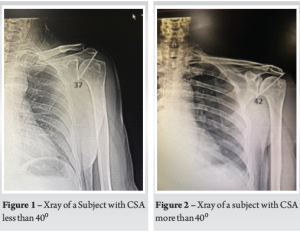

In this study, a total of 40 patients were enrolled. They were divided into two groups of 20 each based on CSA calculated using True AP view X-rays of the shoulder (Fig. 1 and 2). The age and gender difference between the two groups was not statistically significant (Table 1). The average score on the VAS before rehabilitation was 7.4 in group A and 7.5 in group B. It was statistically insignificant in the first 2 follow-ups after rehabilitation, but there was a statistically significant decrease in VAS score in group A (CSA < 40°) when compared to group B (CSA > 40°) patients at 12 weeks after rehabilitation (Table 2).

A true anteroposterior (AP) with visible joint space and only minimal overlap between the posterior and anterior rim of the glenoid is taken. A line connecting the superior and inferior bony margins of the glenoid is drawn, and another line is drawn from the inferior bony margins of the glenoid to the most lateral border of the acromion. The angle formed between these two lines is CSA.

The critical shoulder angle (CSA) is a key anatomical parameter that has gained attention in recent years. CSA is defined as the line connecting the superior and inferior bony margins of the glenoid and a line drawn from the inferior bony margins of the glenoid to the most lateral border of the acromion [7]. Studies suggest that a CSA > 40° may predispose individuals to subacromial impingement and rotator cuff pathology. However, limited research has investigated the role of CSA in rehabilitation outcomes. We aim to analyse whether CSA influences the effectiveness of rehabilitation in managing SIS. Specifically, we hypothesize that patients with a CSA < 40° (Group A) will respond better to rehabilitation, whereas those with a CSA > 40° (Group B) will have poorer outcomes due to altered biomechanics leading to increased subacromial impingement.